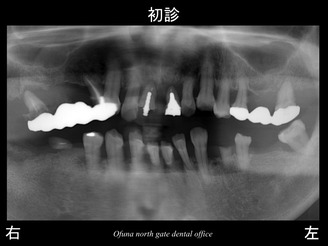

虫歯!

歯周病!

歯がない部分がある!

噛み合わせのズレが起こっている!

等さまざまな問題があります。

多くの歯が初診時にすでにグラグラです。

指で触っても取れそうな歯も多くあります。

下顎右側の奥歯がないことからも 噛むことも困難になっています。